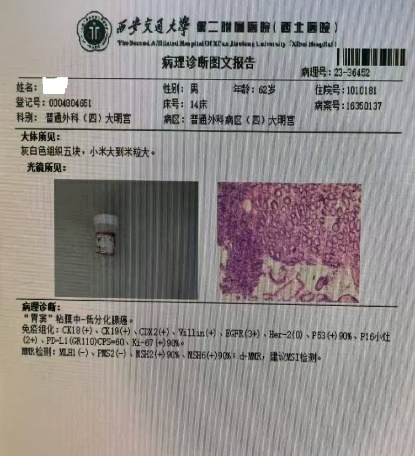

老年患者郑某某,男,60多岁,以“上腹部胀满不适1月余” 之主诉于2023年12月入住老年普外科大明宫院区(普外科四病区)王志东教授团队组。入院行胃镜检查显示胃窦癌,胃潴留,慢性萎缩性胃炎,反流性食管炎。病理活检示胃窦粘膜中-低分化腺癌(图三所示)。上腹部增强CT回报示胃窦、横结肠及其间隙内近9cm肿块型肿瘤,结肠侵犯可能,如图一所示。术前临床分期:cT4bN2M0(IIIb期)也就是通常称呼的局部晚期胃癌。将术前检查评估情况告知家属后,听到局部晚期胃癌的噩耗,家属近乎绝望。王志东教授团队耐心的和病人及家属沟通后,联合肿瘤科、影像科、老年医学科等进行了肿瘤多学科诊疗和老年病多学科诊疗(MDT)后,对该患者实施了6个周期的化疗和PD-1免疫治疗,期间患者适应性良好,未出现严重不良反应。

2023年12月术前胃镜病理结果 胃窦中低分化腺癌